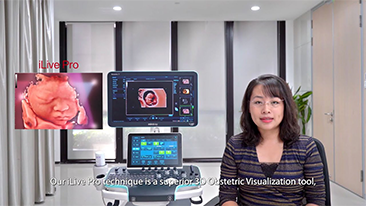

Geburtshilfe